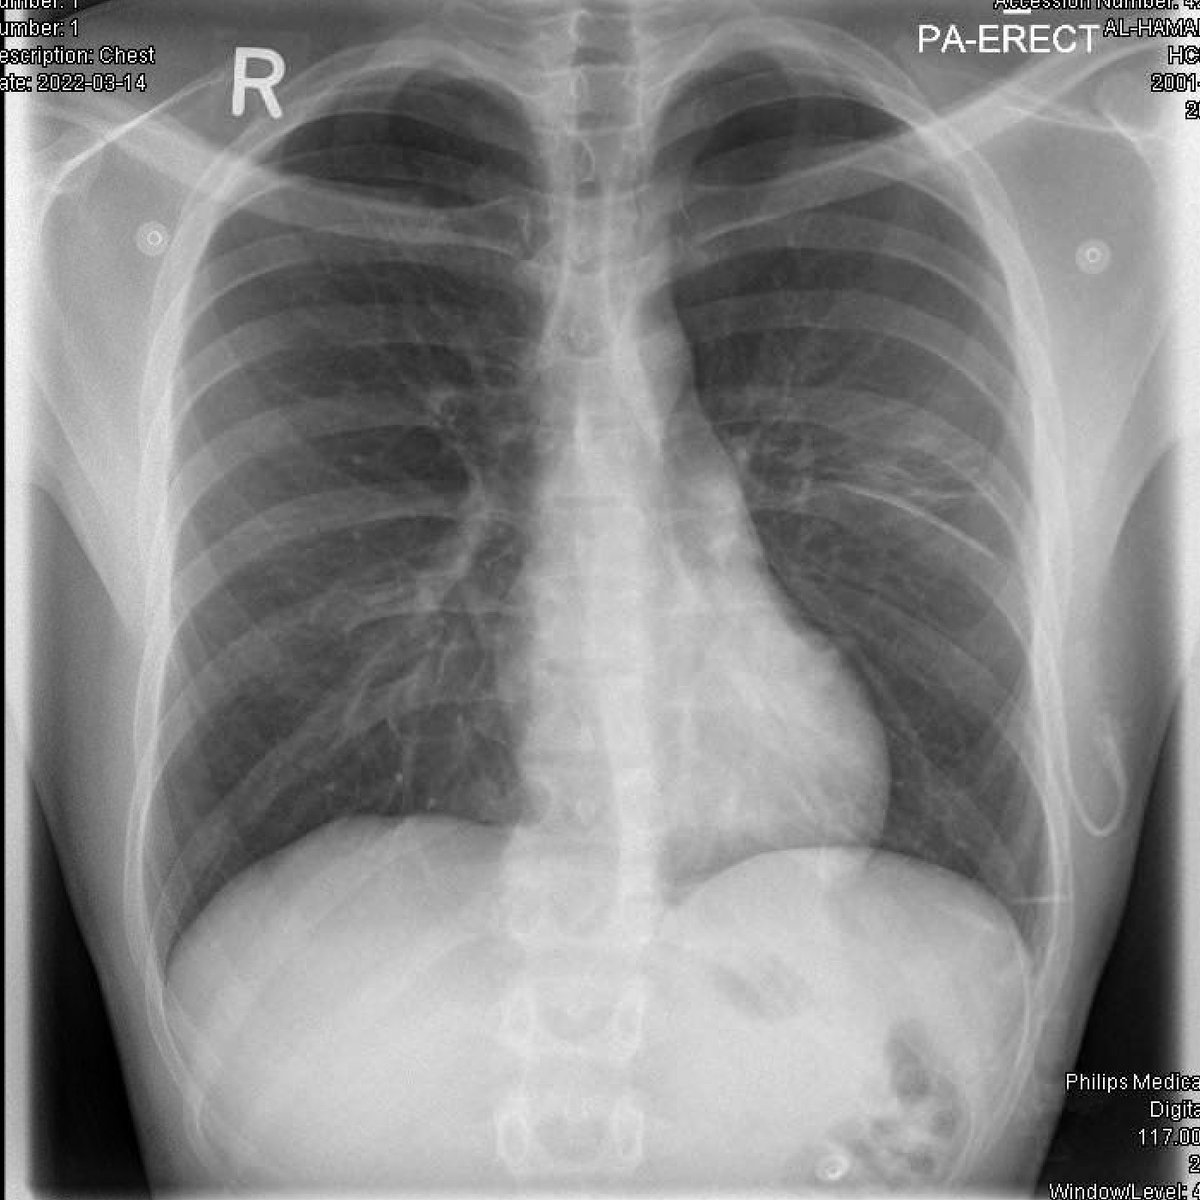

3/n therefore CXR was not a surprise -